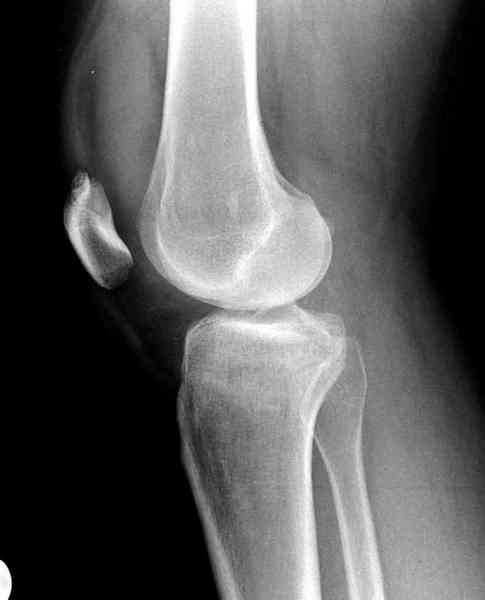

Как всегда прекрасная презентация. Совершенно согласен с необходимостью сохранять мениск и вообще согласен со всем, кроме одного. Фиксация должна проводиться после правильно выполненной репозиции. Главная цель репозиции - это восстановить высоту наружного мыщелка. В норме наружный мыщелок выше внутреннего на 4-5 мм на снимке в переднее заднем направлении АР.

Необходимость репозиции возникает при снижении высоты от 3 до 5 мм по разным источникам. По моему опыту 4 мм. Если не восстановить высоту мыщелка возникает вальгизация коленного сустава с относительным расслаблением передней крестообразной связки. При этом развивается нестабильность коленного сустава из-за недостаточности ПКС.

По этому если фрагмент большой есть необходимость репозиции дистального угла и фиксация пластинкой против соскальзывания ANTIGLIDING PLATE. Если перелом фрагментарный? то очень помогают описанные субхондральные шурупы RAFT, но

чтобы сохранить высоту суставной площадки шурупы одним концом должны опираться на пластинку а другим - на кортекс по внутренней стороне. Идеально сочетание ANTIGLIDING BUTRESS PLATE + RAFT SCREWS.

На представленном после операционном снимке нет репозиции, на что указывает низкое положение тибиального плато и перекрытие кортикальных пластинок в метафизарной части - указано стрелкой. Обычно чрескожную фиксацию я применяю

при переломе без депрессии отломка, или если после СТ понятно, что можно сделать закрытую репозицию, то шуруп с шайбой можно установить прямо в угол, что предотвращает скольжение отломка.